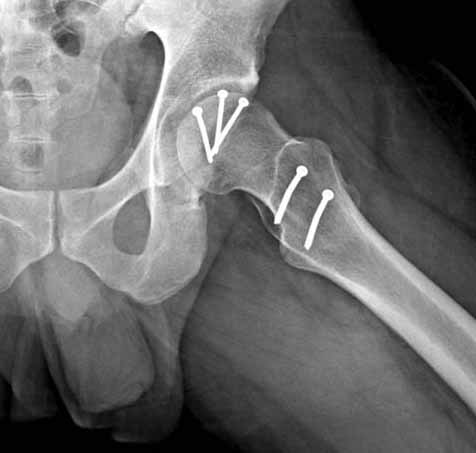

При сопутствующем переломе головки с ацетабулум, тогда артротомия из того доступа, который позволит фиксировать перелом впадины и фиксировать головку шурупами. На сегодня Headless Screw Synthes имеет преимущества перед другими, но при отстутствии их можно сделать обычными 3.5 мм., только головку надо утопить. При изолированном переломе доступ через trochanteric flip approach, который позволяет вывихнуть головку из ацетабулума и свободно работать без риска АВН. В вашем случае можно из переднего Smith Petersen доступа, потому что осколок спереди.

Представлены несколько вариантов фиксации: первый случай перелом головки с задним краем, операция из заднего доступа Кохер, а второй случай изолированный перелом головки - из трохантерного доступа.